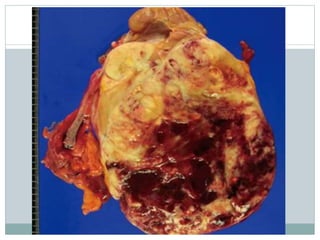

Gross  Tan togray, friable cut surfaces  Hemorrhage and necrosis common  May display cystic change with necrotic, semiliquid contents

• #8 Gross pathological image from radical left nephrectomy demonstrates large mass in lower pole of kidney. Cut-surface shows pinkish yellow mass with internal hemorrhage and cystic change.